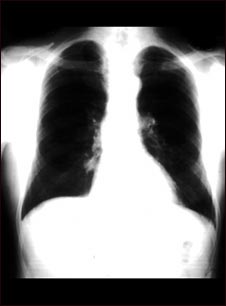

Nódulo pulmonar: vista frontal en la radiografía de tórax

Nódulo pulmonar - Vista frontal de la radiografía de tórax

Ésta es una radiografía del tórax que muestra una masa en la parte inferior del pulmón derecho, cerca al corazón (se puede observar del lado izquierdo de la imagen).